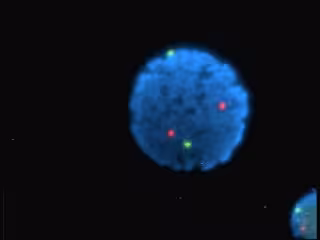

Un grupo de la Universidad Autónoma de Madrid ha estudiado, mediante técnicas ópticas y electroquímicas, la interacción de dos colorantes con ADN, y, como resultado, han descubierto que es posible utilizar estos colorantes como indicadores químicos de la presencia de mutaciones.

Los resultados, publicados en 'Bioelectrochemistry', fueron aplicados al desarrollo de un biosensor electroquímico que ha permitido detectar, de forma rápida y sencilla, dos de las mutaciones genéticas más comunes asociadas a la fibrosis quística.

Según explica Encarnación Lorenzo, directora del Grupo de Investigación en Sensores Químicos y Biosensores de la UAM, "este biosensor está basado en los colorantes Safrina y Azure A, y es útil para detectar secuencias específicas de ADN, o la presencia de mutaciones en las bases de las mismas".

"El método se ha aplicado con éxito a la detección de las mutaciones más comunes, la 'F508del' y la 'p.Gly542Stop', en el gen regulador de la fibrosis quística, en muestras reales extraídas de células sanguíneas de pacientes que sufren la enfermedad", agrega la investigadora.